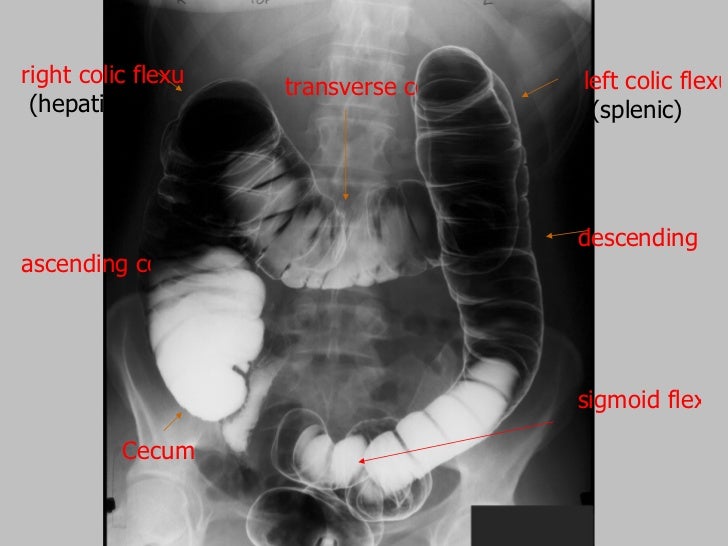

For the rest, check out our digestive diseases and conditions section.The equid gut has a small stomach, relatively short small intestine and a voluminous large intestine. When it comes to the latter, learn how DNA health testing could reveal whether you’re genetically predisposed to this kind of gluten intolerance. Various diseases can lead to problems in our intestines-from IBD and colon cancer to celiac disease. The serosa forms a smooth, slimy outer layer so that the intestines do not become inflamed from contact with other organs or muscles during digestion and movement of the body. The outermost layer of the intestines is the serosa, which is made of simple squamous epithelium. Intestinal movements such as peristalsis and segmentation help to move food through the intestine and churn the food so that it has contact with the intestinal walls. The muscularis layer surrounds the submucosa and provides several layers of smooth muscle tissue to move the intestines. In the small intestine, many tiny folds called villi increase the surface area of the mucosa so that the contact between food and mucosa is greatly increased, subsequently allowing more nutrients to be absorbed by the intestines.ĭeep to the mucosa is the submucosa layer that contains many blood vessels, nerves, and connective tissues that support the mucosa. The epithelial cells of the mucosa absorb the nutrients and water from digested food and transfer these substances to blood in nearby capillaries. Mucus produced by the mucosa lubricates the interior of the intestines to prevent friction from food passing through the lumen, or hollow portion of the intestine. Mucosa is made of epithelial tissue containing mucus-secreting goblet cells. The innermost layer of the intestines is the mucosa. During defecation, the anal sphincter muscles of the anal canal relax to allow feces to exit the body.The rectum stores feces until they are ready to be defecated (eliminated from the body).Next, the descending colon carries the feces inferiorly to the S-shaped sigmoid colon and rectum. The transverse colon then carries feces transversely from the right side of the abdomen to the left side, where it enters the descending colon. The ascending colon carries feces superiorly from the cecum to the transverse colon. Fecal matter passes from the cecum into the colon, the largest region of the large intestine.The appendix is attached to the inferior end of the cecum and is believed to store beneficial bacteria that help break down undigested food. Fecal matter entering the large intestine from the ileum passes into the cecum before being pushed superiorly into the ascending colon. The cecum is a pouch-like dead-end passage that branches inferiorly from the end of the ileum.Our large intestine consists of 4 major regions: the cecum, colon, rectum, and anal canal. These intestinal walls also absorb vitamins released from the fermentation of feces by bacteria living in the large intestine. The smooth walls of the large intestine absorb water from fecal matter. It receives fecal matter from the small intestine through the ileocecal sphincter. The large intestine is about 2.5 inches in diameter and about 5 feet long in a living body. Any last nutrients that were not absorbed in the jejunum are absorbed in the ileum before the food passes into the large intestine. Finally, food passes into the ileum, the longest region of the small intestine.